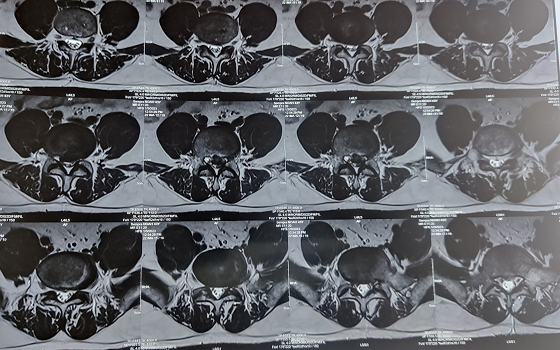

Dr. Somashekar D is an experienced spine surgeon in Bangalore. He is currently practising as a Consultant - Spine Surgery at Manipal Hospital Jayanagar, Bangalore. With nearly 10+ years of expertise in spine care, Dr. Somashekar has established himself as a highly skilled spine surgeon, contributing to over 1,500+ spine surgeries independently, ranging from simple decompressions to complex spinal reconstructions. His practice is deeply rooted in precision-based techniques and evidence-guided clinical protocols, ensuring both safety and long-term functional outcomes for his patients. He is a top spine surgeon in Jayanagar.

We offer comprehensive treatment for spine issues that is on par with any leading spine center worldwide. Our services encompass both non-surgical and surgical treatments tailored to address your specific condition. Our expertise covers a wide range of spine surgeries, including minimally invasive spine surgery, cervical spine surgery, scoliosis surgery, and complex spine surgeries.

• Disc problems

• Sciatica

• Degenerative spine disease

Covers a wide range of spine surgeries, including complex spine surgeries.